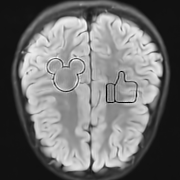

This result implies that random noise can also produce undesirable effects. In Fig. 3 we show several examples of this effect. For the first DL method, mean zero Gaussian noise causes the NN reconstruction map to hallucinate, by artificially removing an image feature (indicated by the red arrow). In the second case, certain image independent, small mean Gaussian noise causes severe instabilities in the recovered image. Notice that the noise causes the second DL method to exhibit completely nonphysical artefacts, which could be easily identified by a practitioner as a failure mode. Yet for the first method it creates seemingly realistic artefacts (hallucinations). Such pernicious artefacts may be impossible to detect.

A.3 Fig. 3

This figure consists of two experiments with two different NNs. We cover both in turn.

In the four leftmost images, we consider the DeepMRI-Net from [66]. This NN is composed of a cascade of U-Nets and data consistency layers. It has been trained on cardiac images, such as the one shown in the figure. The sampling operator is a subsampled two-dimensional Fourier transform, whose sampling pattern is shown in Fig. 7. The noise vector used in the experiment was created as , where is a zero-mean complex-valued Gaussian noise vector. Since the mean of a Gaussian random variable is unchanged by a linear transformation, the noise vector still has zero-mean.

The four rightmost images are from [7]. Code is available at https://github.com/vegarant/am_AI_hallucinating. Here we consider the AUTOMAP network from [82]. This NN was trained by the authors of [82] on brain images from the MGH–USC dataset [27]. It was trained using Fourier sampling with 60% subsampling. In [7], the perturbations

Here , and , are zero-mean Gaussian vectors. The vectors , , are worst-case noise vectors computed for an image that differs from the image used in the experiment. This makes the mean of the Gaussian noise vector image independent. The image used to compute the worst-case perturbations is shown in Fig. 6.